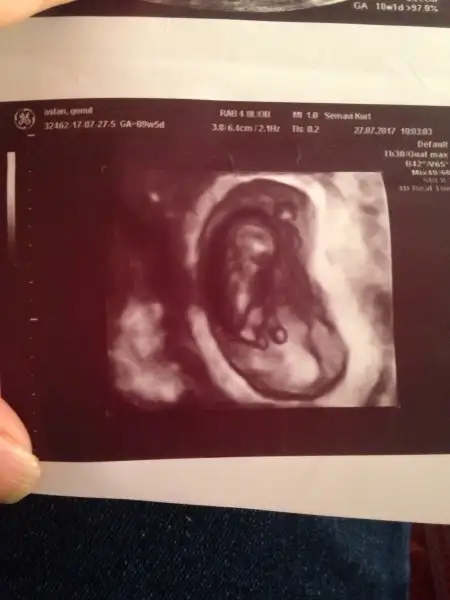

Kızlar bakın üst solda oğlan oğlum :)

Altta sağ da olan ise bu gebeliğim şuan 14+0 hamileyim Cuma kontrol var bakalım bu ne olcak tutcak mı :)